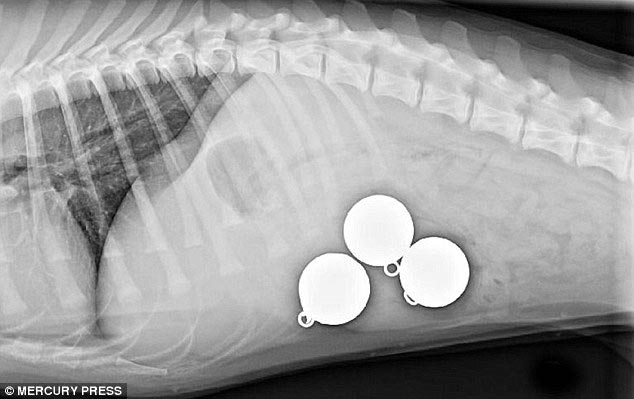

Лабрадор, проглотивший 3 массивных рыболовных грузила

![Что на ужин? Рентгеновские снимки животных, с шокирующими предметами извлеченными из их желудков предметы извлеченные из желудков животных, рентгеновские снимки животных съевших предметы, необычные предметы съели животные]()

Три 200-граммовых грузила извлеченные из его желудка